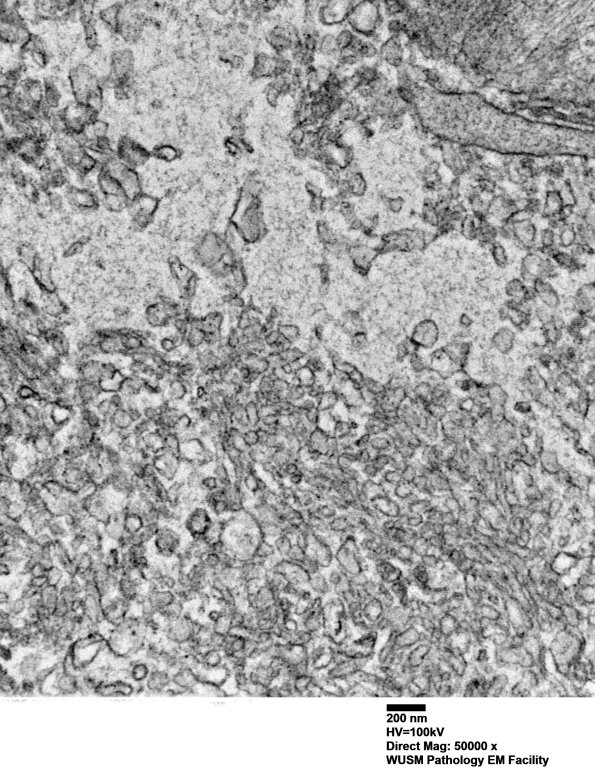

Higher magnification of image #16C3. (electron micrograph)